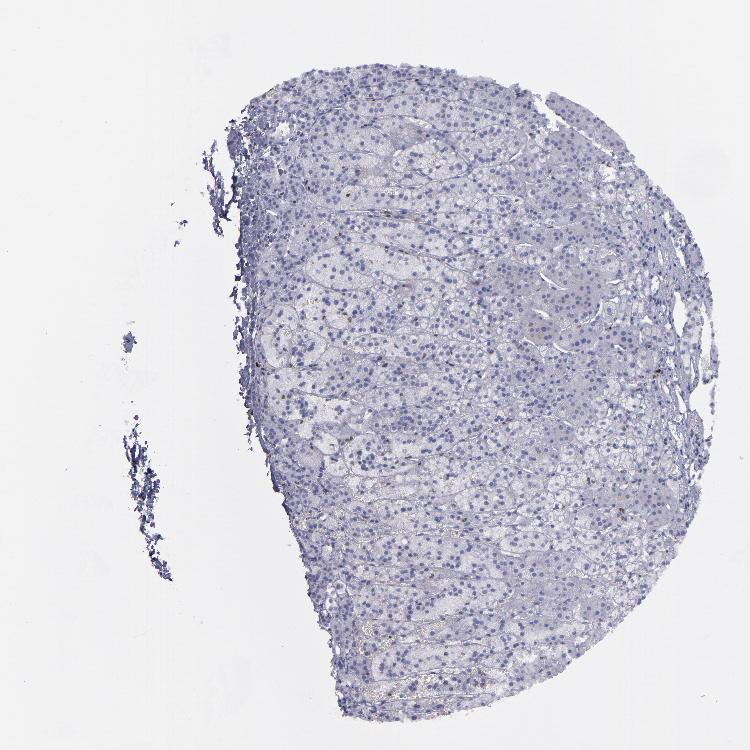

ADRENAL GLAND - Antibody stainingi

Antibody staining in the annotated cell types in the current human tissue is reported as not detected, low, medium, or high, based on conventional immunohistochemistry profiling in selected tissues. This score is based on the combination of the staining intensity and fraction of stained cells.

Each image is clickable and will lead to virtual microscopy that enables deeper exploration of all samples and also displays staining intensity scores, fraction scores and subcellular localization as well as patient and tissue information for each sample.

Antibody HPA002267Antibody HPA002531Antibody CAB013480

Glandular cells LowLowHigh